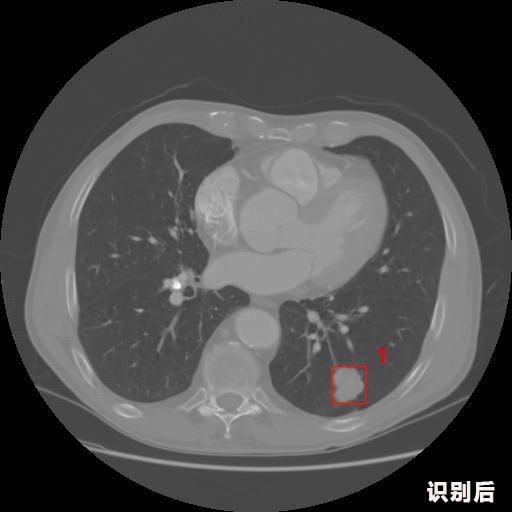

英特健康A(chǔ)I深度學習醫(yī)療圖像識別系統(tǒng)案例_胸部CT

1.發(fā)現(xiàn)肺結(jié)節(jié)的可能性為95.56%---位于框指數(shù)位置:[331.70554 366.13406 365.21707 403.96234]